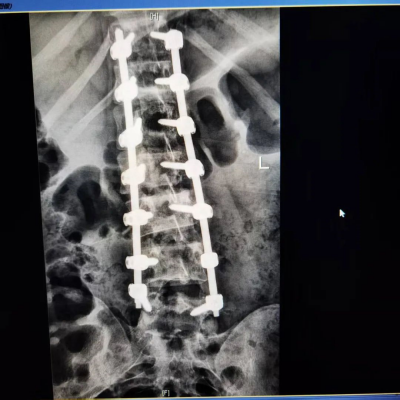

对于小林这样错过保守治疗时机的患者,手术成为重要选择。术中,脊柱外科二区主任曾浩带领的医疗团队运用实时电生理监测技术,凭借丰富的临床经验,精准避开神经组织,通过在小林的脊柱两侧植入钉棒系统,像“牵引复位”般将弯曲的椎体逐步矫正,全程出血量不足200毫升。这种高难度手术对医生的解剖学功底、操作稳定性要求极高。